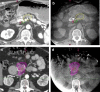

Standard doses of conventionally fractionated radiation have had minimal to no impact on the survival duration of patients with locally advanced unresectable pancreatic cancer (LAPC). The use of low-dose stereotactic body radiation (SBRT) in 3- to 5-fractionshas thus far produced a modest improvement in median survival with minimal toxicity and shorter duration of treatment, but failed to produce a meaningful difference at 2 years and beyond. A much higher biologically effective dose (BED) is likely needed to achieve tumor ablation The challenge is the delivery of ablative doses near the very sensitive gastrointestinal tract. Advanced organ motion management, image guidance, and adaptive planning techniques enable delivery of ablative doses of radiation (> = 100Gy BED) when more protracted hypofractionated regimens or advanced image guidance and adaptive planning are used. This approach has resulted in encouraging improvements in survival in several studies. This review will summarize the evolution of the radiation technique over time from conventional to ablative and describe the practical aspects of delivering ablative doses near the GI tract using cone beam CT image (CBCT) guidance and online adaptive MRI guidance.